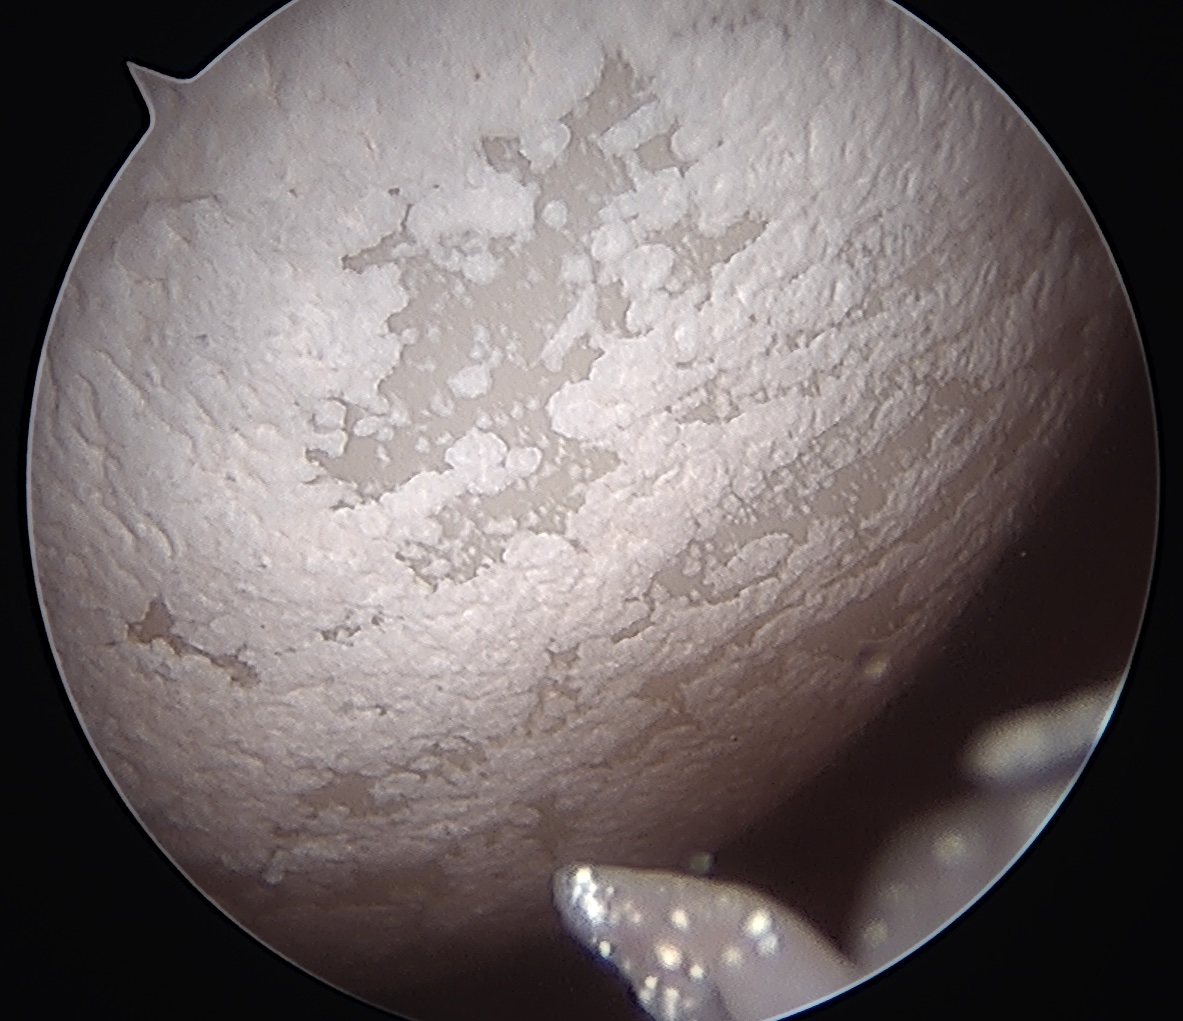

Arthroscopy